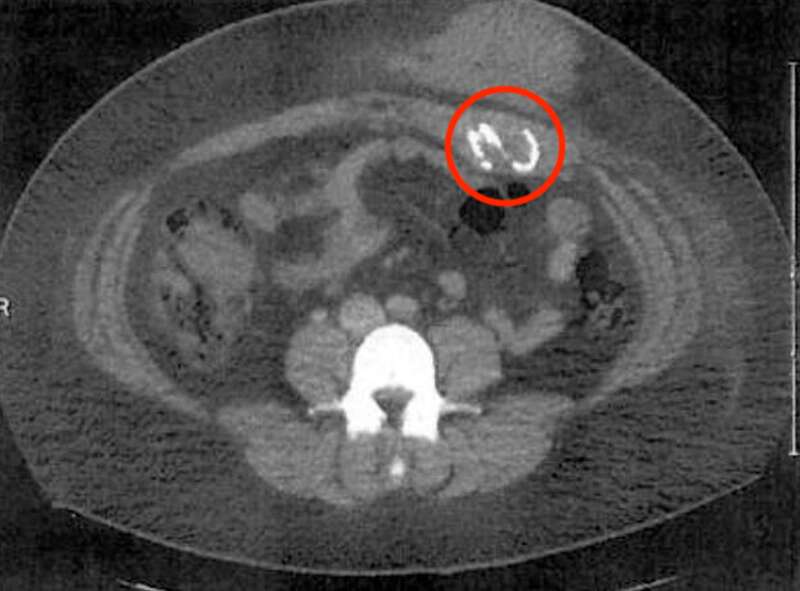

Después de nueve meses, Abney-Acosta buscó una segunda opinión. El nuevo cirujano hizo un gesto hacia algo que los otros médicos habían perdido en su CT-scan —, la forma de una S curva dentro de su abdomen.

“Eso es una esponja,”, dijo.

Una esponja quedó dentro de Emily Abney-Acosta después de una cirugía en Texas en 2018. Aparece en esta radiografía en el círculo rojo.Contribuido por Emily Abney-Acosta